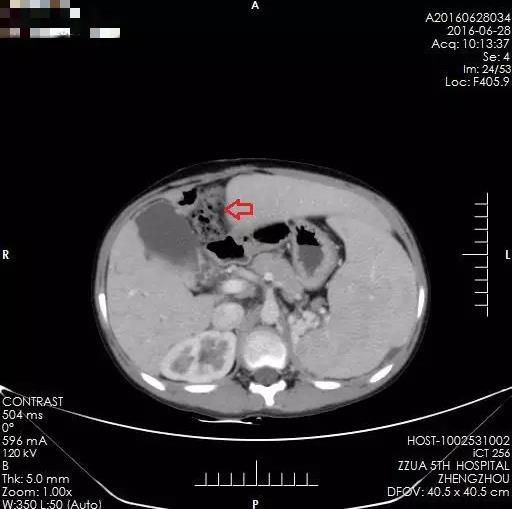

术前多发肝内胆管囊样扩张

术后2年,箭头所示为肝肿瘤切除后

术后2年,箭头所示为多发肝内胆管囊样扩张